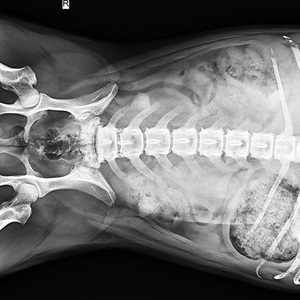

“宠物看病比人看病贵”、“费用不合理”、“过度医疗”......宠物医疗总是饱受争议。据报道,中国城镇养宠用户已超过7000万人,宠物犬猫的数量已经超过1亿只。《中国宠物行业白皮书——2022年中国宠物消费报告》显示,在国内,宠物主花在狗身上的年平均消费大约是2882元,花在猫身上的年平均消费大约是1883元。在宠物的主要消费市场中,医疗排在食品之后,市场份额为29.1%。在医疗之中,诊疗占比最大,其次才是药品、体检和疫苗。

近些年,中医也被应用在了宠物身上。让我们跟随摄影师的镜头,走进宠物诊疗室,一探宠物的看病故事。